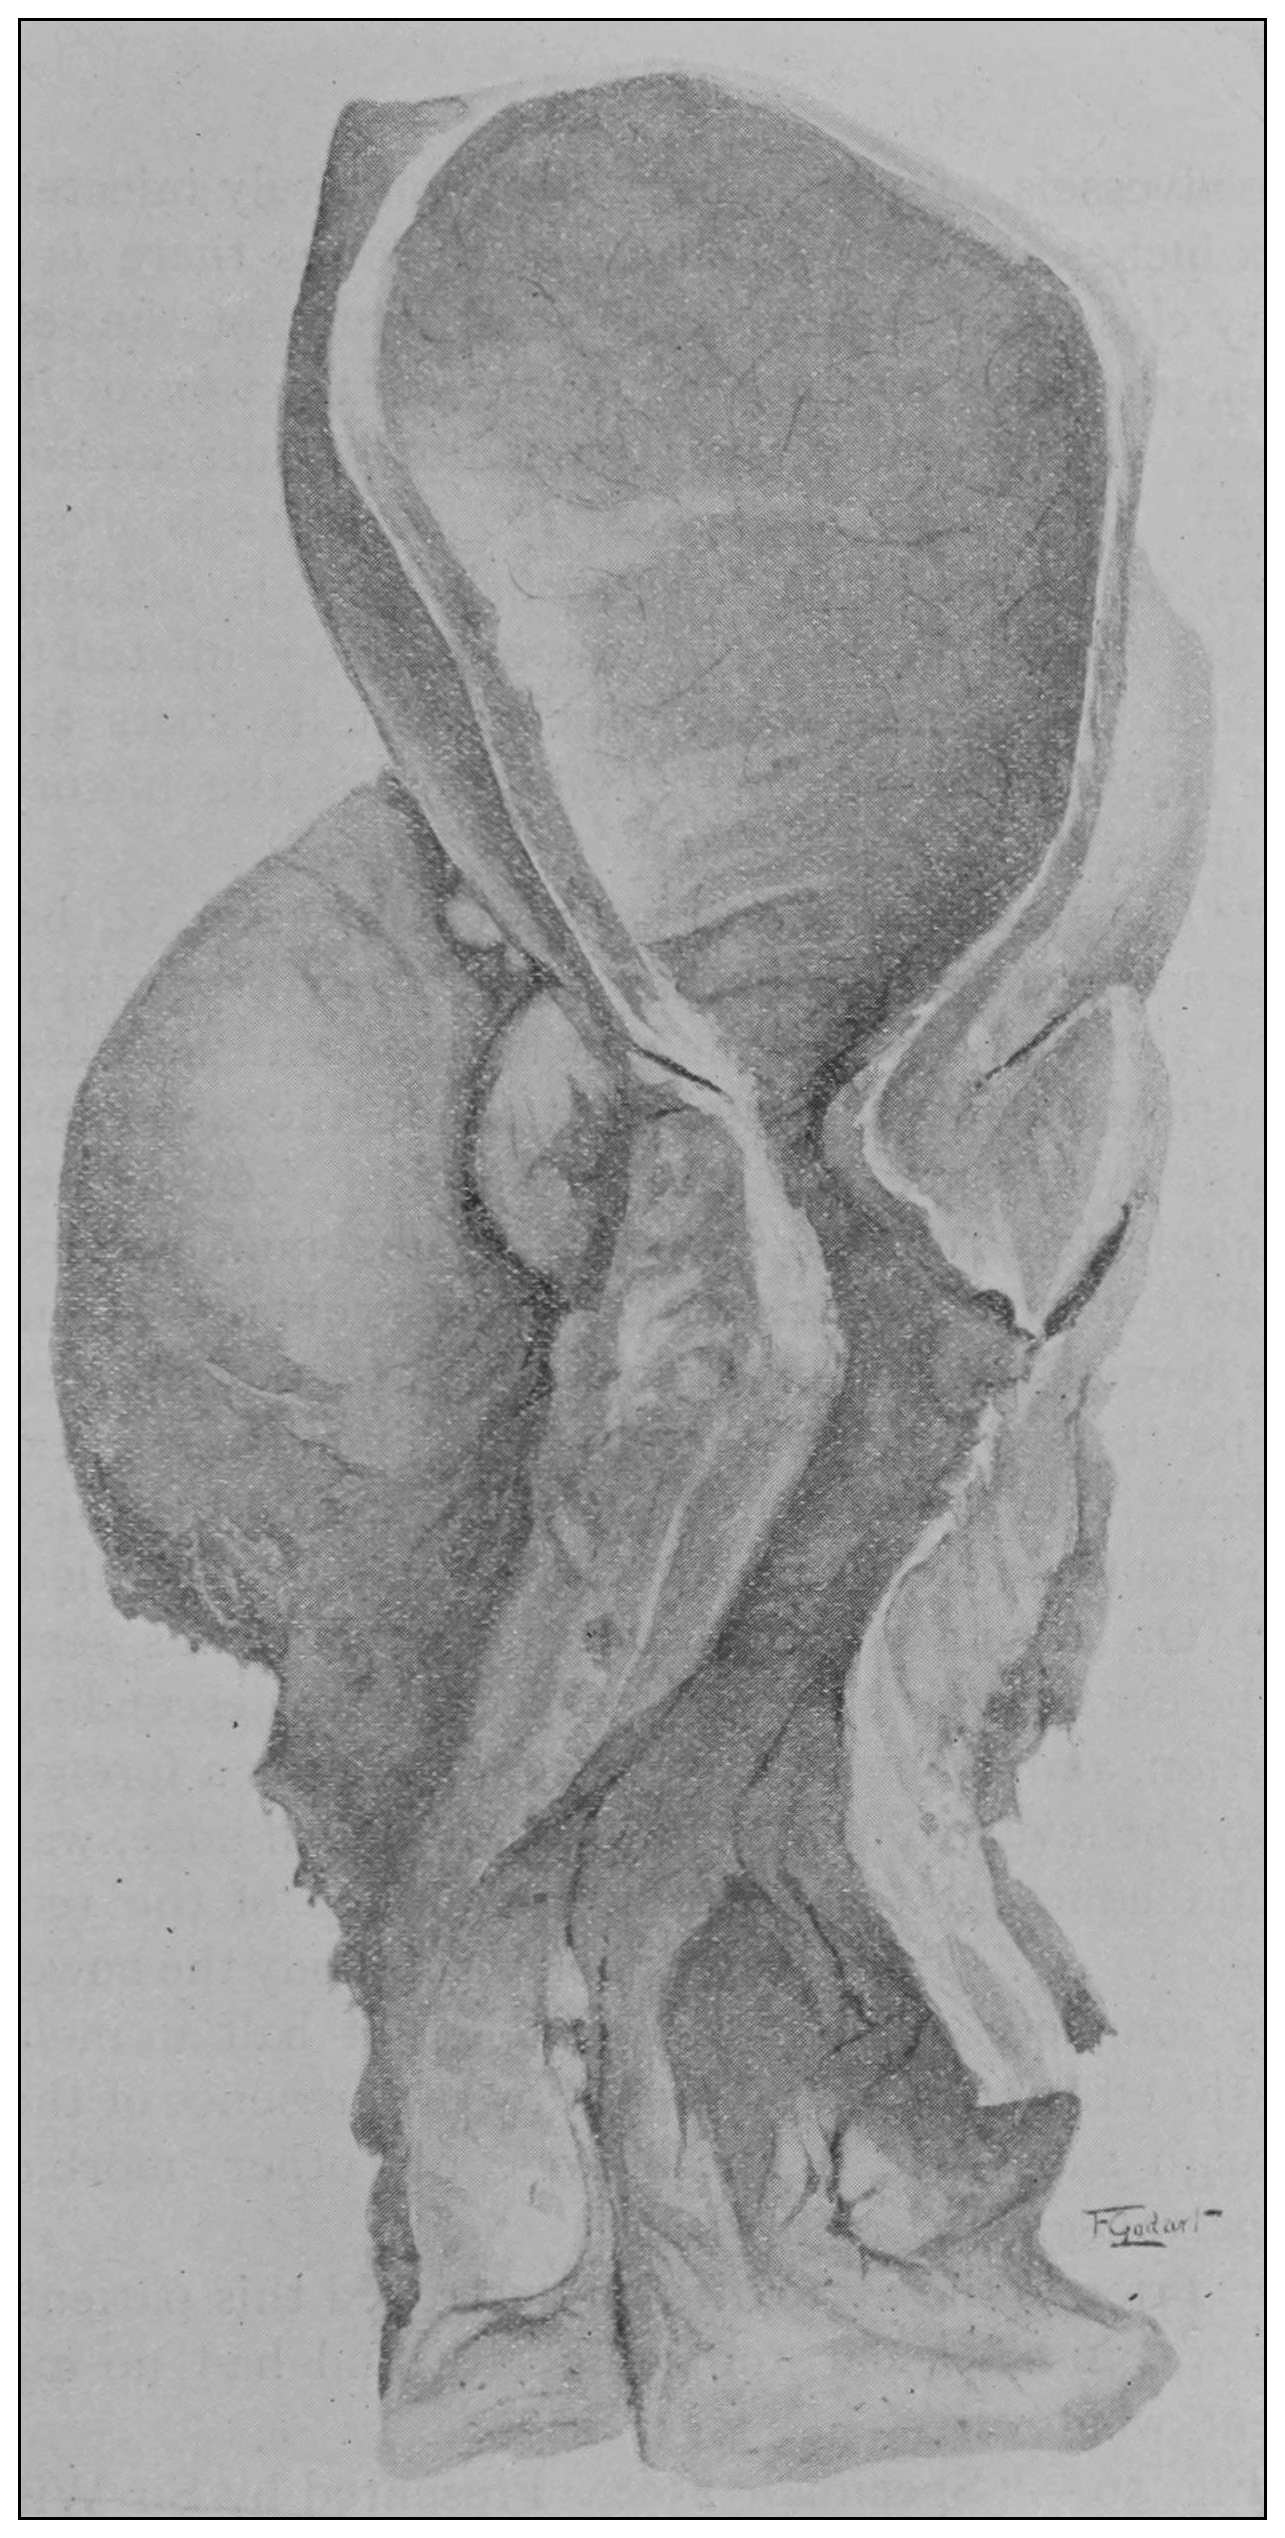

Fig. 19.—Drawing of specimen No. 281 in the Anatomical Museum of the Royal College of Surgeons, London. The dissection was made by Mr. William Pearson. The drawing shows in the lower part of the field the coccyx, in the upper part of the field the pubes.

Fig. 20.—Drawing of specimen No. 284 in the Anatomical Museum of the Royal College of Surgeons, London. The dissection was made by Mr. William Pearson. The drawing shows in the lower part of the field behind the rectum the coccyx, in the upper part of the field the pubes.

The fixed anal rectum begins at the levator ani and coccygeus muscles. The levator ani has its origin at the sides of the bodies of the pubic bones, the coccygeus at the spines of the ischii, and the levator ani has additional origin from the fascia and bony parts on a line between these two points. The fibers of these muscles are directed downward and inward to the fixed anal rectum; many fibers are blended into the contiguous structures of the pelvic floor. The coccygeolevator muscles may be compared to an opened slat-fan, the apex having its place at the anus, and its long border representing the line of origin of the muscles, Fig. 19. The ental sphincter ani muscle, situated a few lines below the levator ani, is made up of an aggregation of the fibers of the circular non-striated muscular intestinal coat, Fig. 20. The ectal sphincter ani striated muscle is situated immediately beneath the external skin. It serves the present occasion to describe the ectal sphincter of the male as a loop of muscle thrown about the terminal end of the rectum and hitched to the terminal bone of the coccyx, and in the female as a longer loop of muscle twisted upon itself so as to make a tandem-loop,[56] which, in the form of the figure eight (8), is thrown about the vagina and terminal end of the rectum.